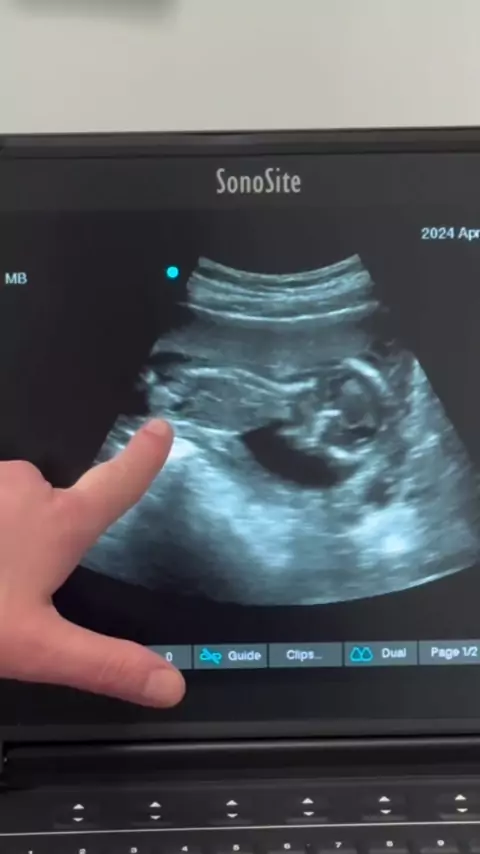

SteffanyDarezzo❄️☃️

Como está sendo o meu pré -natal aqui no Alaska